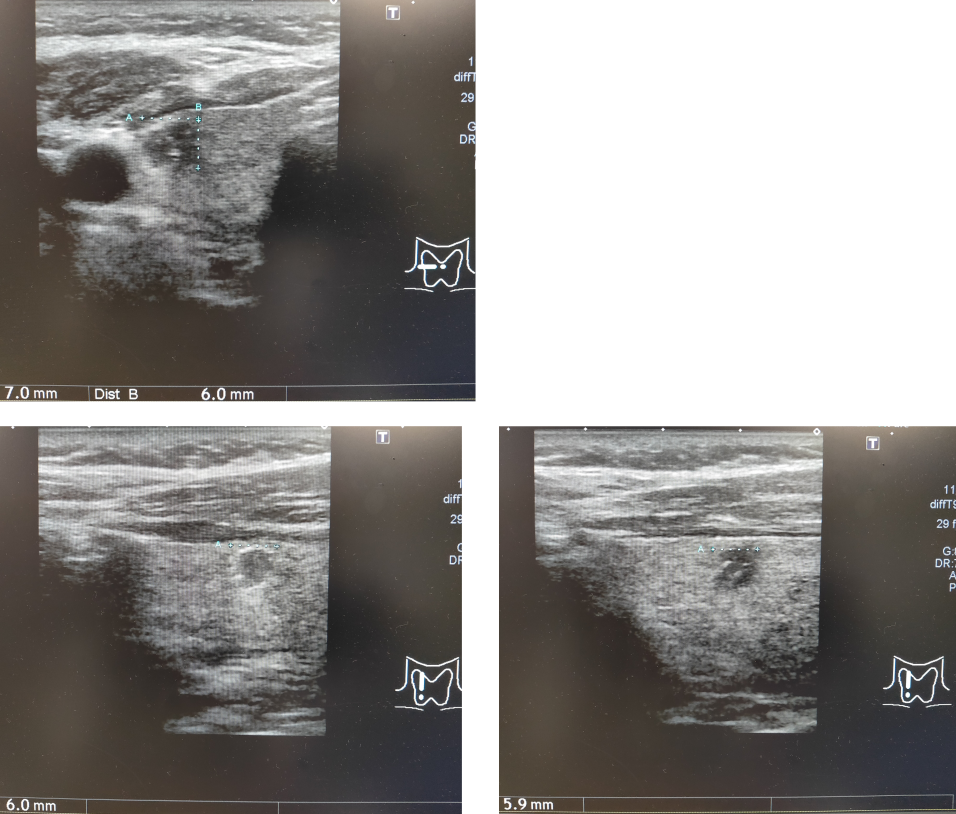

・甲状腺エコー

・穿刺吸引細胞診:クラス5。乳頭癌